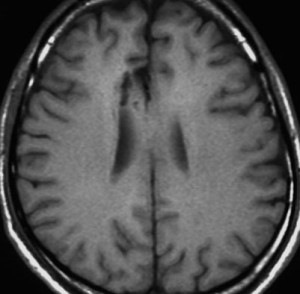

2000年頃の例です。てんかんで発症した20代の女性です。左前頭葉のグリオーマで,手術でほとんどで摘出 subtotal removalして,深部白質に残った病変を経過観察しました。MRIは術後のものです。Ip, 19qはFISHで欠失なし。MIB1は1-2%と低く,MGMTメチレーションなし,diffuse astrocytoma WHO grade 2と組織診断されました。大学病院でしたが当時はIDH遺伝子診断はしておらず,びまん性星細腫グレード2でした。これもまた当時の標準的な考えで,進行があるまでは経過観察としました。

2年後に急激な進行 rapid progressionしました。ガドリニウム増強所見も出現しました。IMRTで59.4Gy/27分割の放射線治療とテモゾロマイド化学療法をしましたが,腫瘍は抑制できませんでした。

放射線治療後も進行して,白質に沿った浸潤伸展をしました。脳幹部橋の右側まで浸潤 invasionしています。この伸展は星細胞系腫瘍の特徴でもあります。